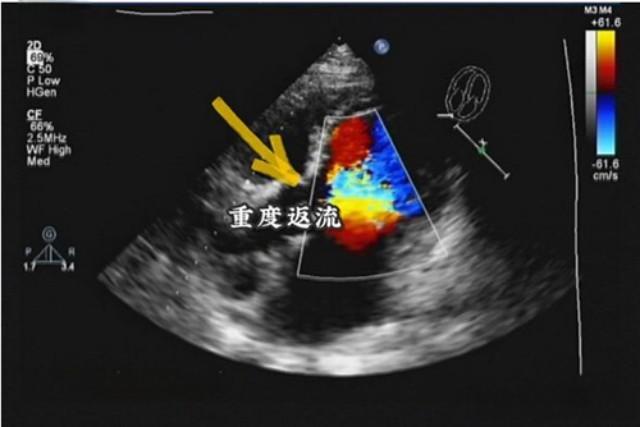

二尖瓣和三尖瓣轻度返流是常见的心脏瓣膜问题。根据美国心脏病学会的数据,约10%的成年人存在轻度瓣膜返流。这种状况通常不会立即引起症状,但需要定期监测以防止病情恶化。

轻度返流通常不需要立即治疗。妙佑医疗国际的专家指出,对于轻度二尖瓣或三尖瓣返流,患者可能不需要治疗。然而,定期进行体检、药物治疗或手术可能是必要的,特别是当病情进展到中度或重度时。

尽管轻度返流通常无症状,但如果不加以控制,可能会导致一些并发症。二尖瓣返流可能导致心房颤动、肺动脉高压和充血性心力衰竭。三尖瓣返流则可能导致房颤和心力衰竭。因此,即使在轻度阶段,也需要密切关注病情变化。